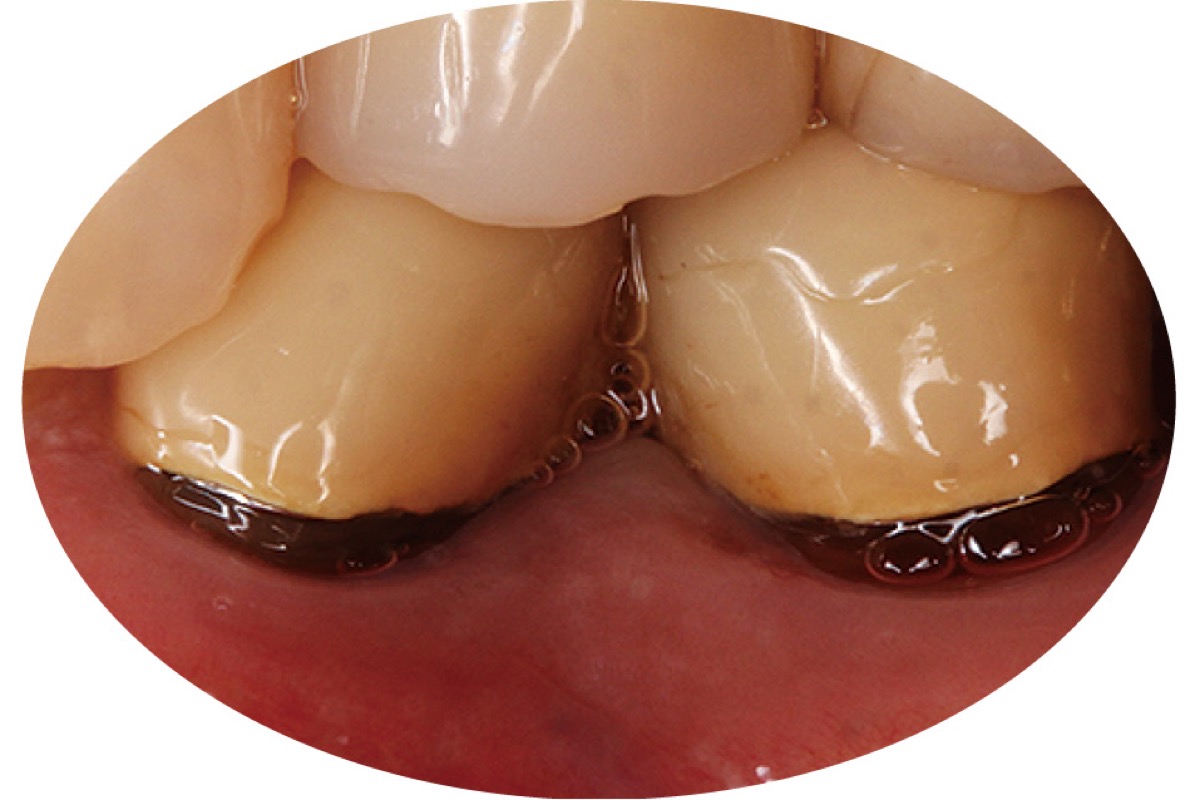

シニア世代に多い口腔内トラブルの一つに「根面う蝕」が挙げられる。

藤沢駅徒歩7分の場所に昨春開院した「藤沢わたる歯科クリニック」の和田航院長によると、加齢や歯周病により歯肉が下がり、丈夫なエナメル質に覆われていない歯根が露出。根面は薄く柔らかい象牙質で酸に弱く溶けやすいため、虫歯が進行しやすい。近年の調査では70代の約65%、80代の約70%が患っており、「折れたり、抜けたり、歯の大部分を失いかねない」と警鐘を鳴らす。

自覚症状が少なく発見しにくい上に、治療は困難。「歯みがきなど家庭でのメンテナンスには限界がある。重症化する前に、歯垢・歯石の除去や高濃度のフッ素塗布などを定期的に歯科医院で受けることが重要。まずは検診で歯の状況を把握し、大切な歯を守りましょう」と和田院長。